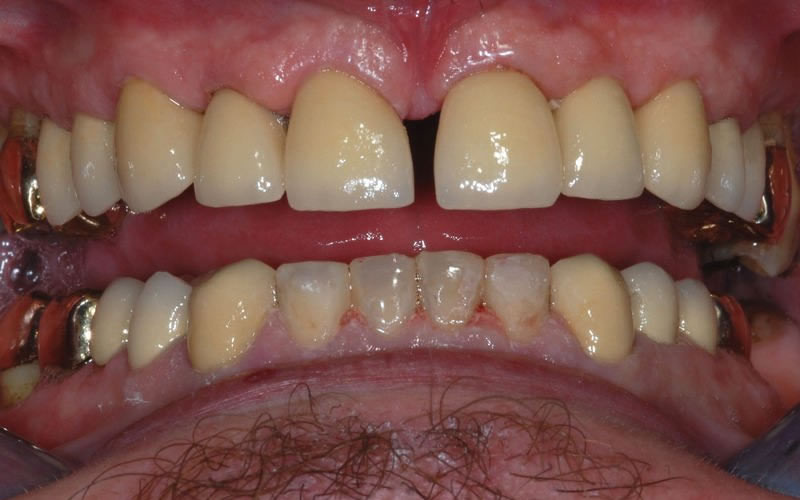

Case Studies

Dental Crowns (7 images)

Upper crowns and lower composites (4 images)